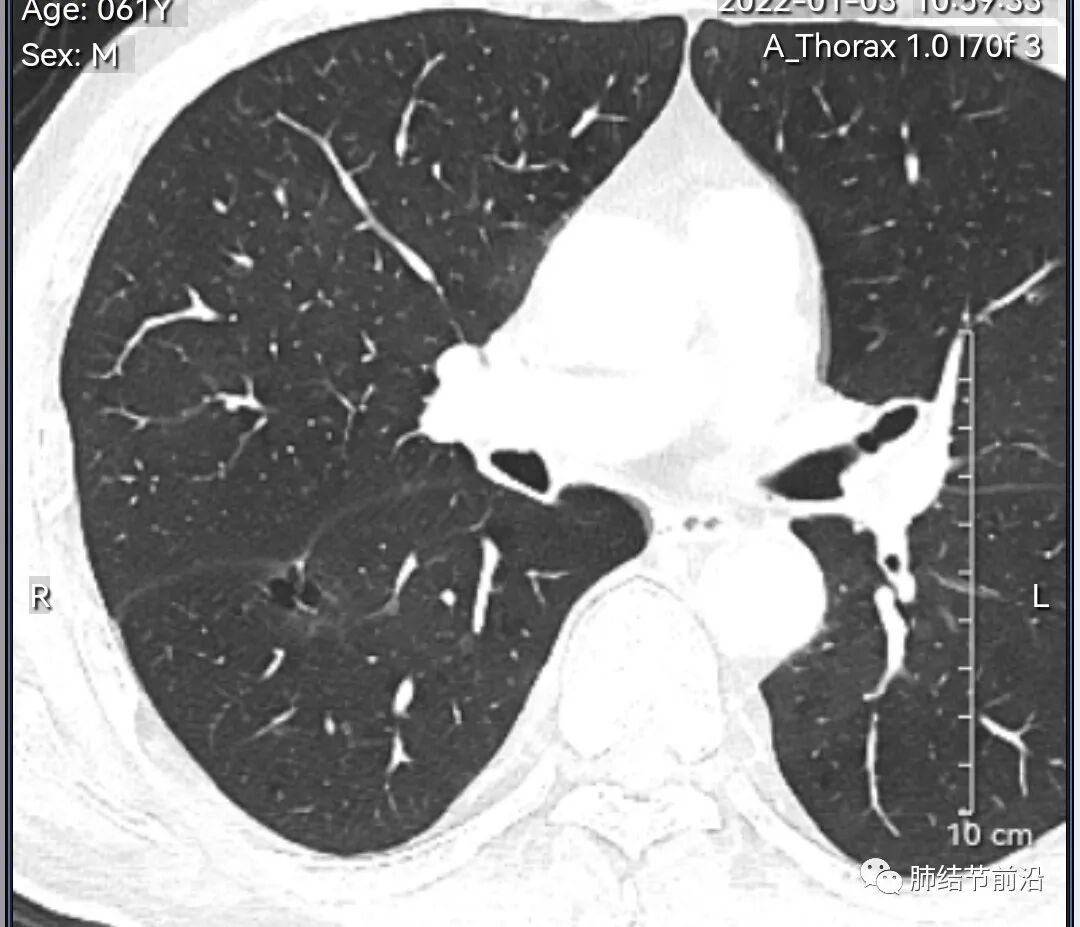

男性,67岁,重度吸烟史。CT发现右下肺囊腔。来看一下这个CT的特点:

该囊腔形态非常有特点,和常见的圆形肺大泡有很大的区别。

1.囊腔中央实性成分,周围有磨玻璃影。

2.囊腔中央有血管。

3.囊腔外周有分叶形态。

4.囊腔有胸膜牵拉。

出现这几种形态,CT可以确认恶性的腺癌。这个囊腔形成的机制,为肿瘤实性成分堵塞细支气管形成活瓣,肺泡内压力增高破裂行成,因此肺内血管成分保留。由于肺泡压力增高,而呈分叶状。另外,也有肿瘤的胸膜牵拉这一特点。

囊腔周围磨玻璃+囊腔中央血管为特征性表现。如果持续存在,几乎可以100%确认为早期肺腺癌。

建议患者手术切除,术后病理为浸润性腺癌,腺泡型,部分为实体型。IA1期,术后不用治疗。